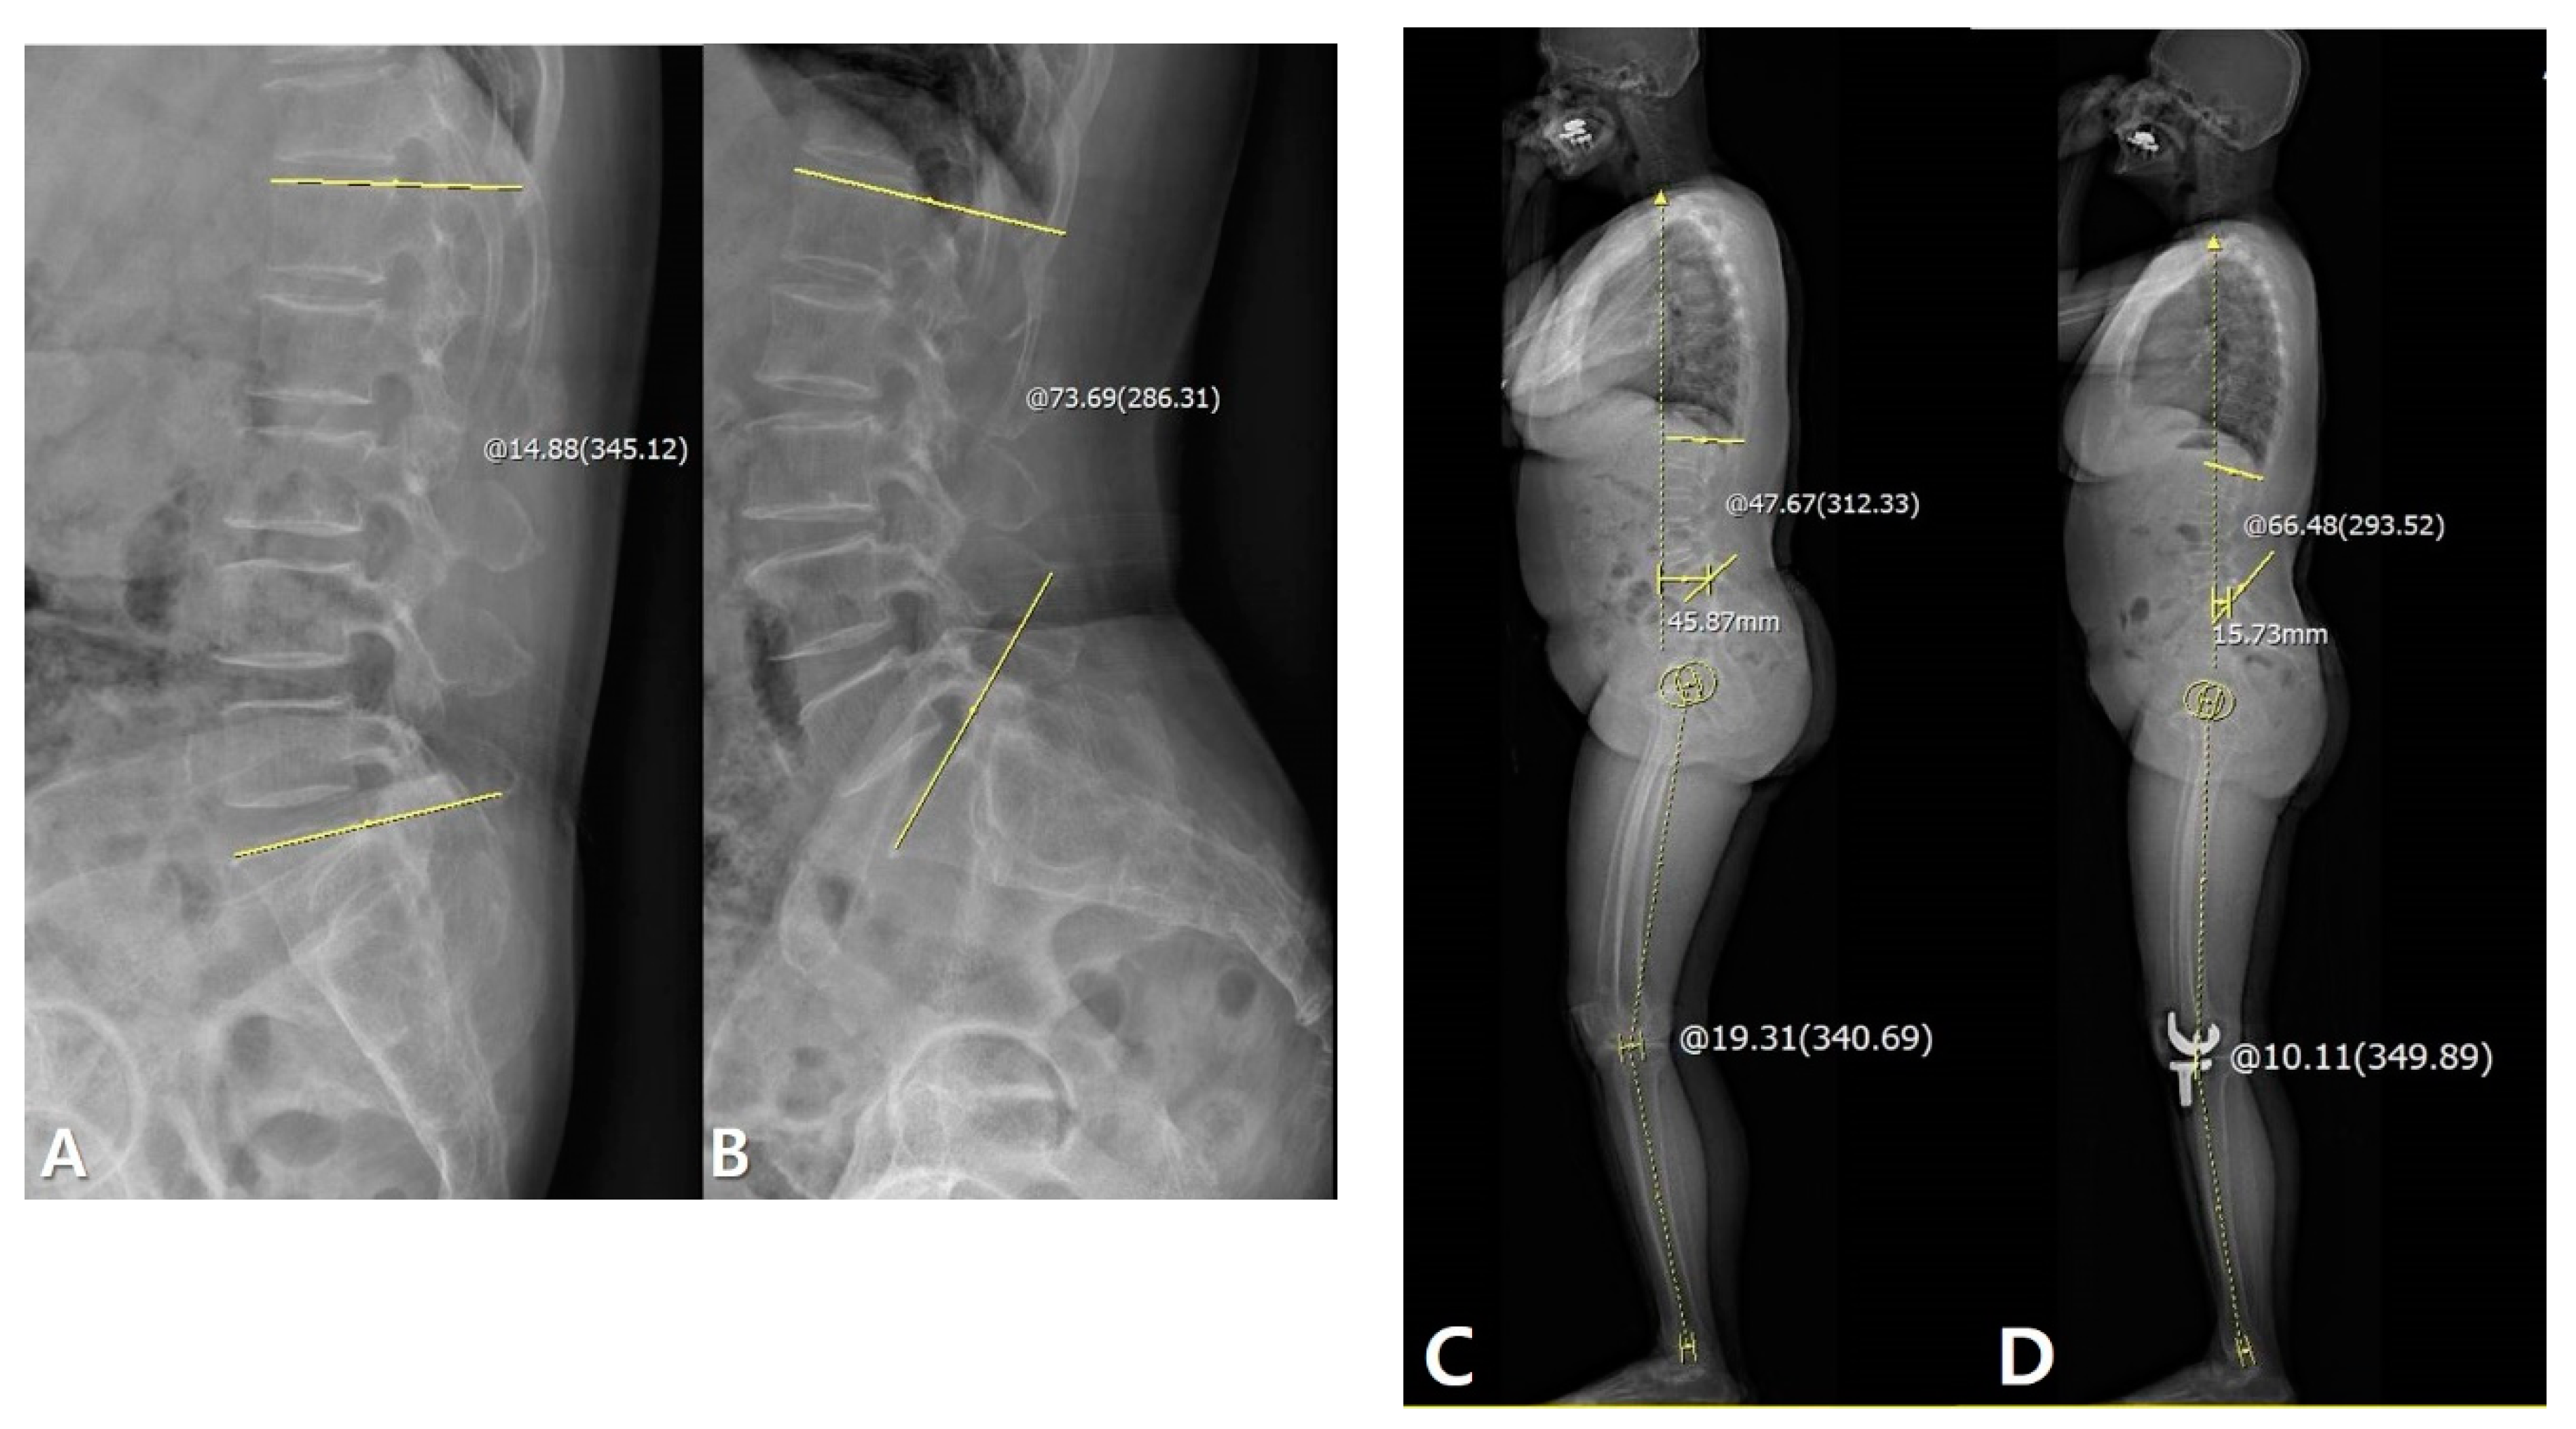

Figure 3. Patient with larger lumbar flexibility (LF) improved sagittal spinal alignment after TKA: Measurement of LF on flexion-extension view: 58.81°. (A) Measurement of LL on flexion view: 14.88°. (B) Measurement of LL on extension view: 73.69°, improved spinal alignment increased LL and decreased line-sacrum distance (SVA). (C) Measurement of the preoperative LL: 47.67° and SVA: 45.87 mm. (D) Measurement of postoperative LL: 66.48° and SVA: 15.73 mm. The yellow line and circle are the measurement about lumbar lordosis, SVA and sagittal HKA.

The correlations between the LF and other sagittal parameters are summarized in Table 2. LF was significantly correlated with ΔLL and ΔSVA between preoperative and 1-year postoperative data (LL: p = 0.039, SVA: p = 0.040; Pearson correlation coefficient (PCC): −0.206 and 0.205, respectively). However, TK, PT, SS, and HKA were not correlated with the LF. Linear regression analysis for the identification of a cause–result relationship revealed that larger LF significantly increased LL and decreased SVA after TKA (p = 0.039, β = −0.155 and p = 0.040, β = 0.681, respectively) (Table 2, Table 3 and Figure 3).

The correlations between the PF and other sagittal parameters are summarized in Table 3. Although there were correlations between PF and ΔSS between preoperative and 1-year postoperative data (p < 0.001, PCC: −0.362), other sagittal parameters were not correlated with the PF. Linear regression analysis for the identification of cause–result relationships revealed that larger PF significantly increased SS after TKA (p < 0.001, β = −0.208) (Table 3 and Table 4, Figure 4).